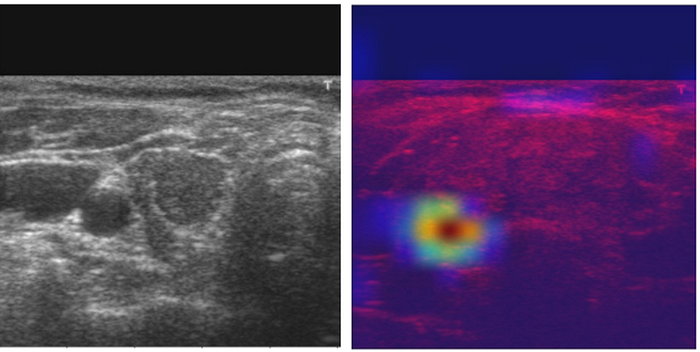

Grad-CAM is a strict generalization of the Class Activation Mapping. Unlike CAM, Grad-CAM requires no re-training and is broadly applicable to any CNN-based architectures. We also show how GradCAM may be combined with existing pixel-space visualizations to create a high-resolution classdiscriminative visualization (Guided Grad-CAM). In this study ,we used GradCam method to examine results.

In figure 5 , as can be seen, the model targetted tyhriod tumor for classification. This shows that the model focuses the tyhriod tumor for the classfication

In this study, the thyroid nodules classified 6 different classses which are 1 (Benign) , 2 (Benign) ,4a (Malign) , 4b (Malign),4c (Malign) ,5 (Malign). Data augmentation is a technique used to increase the number of training data artificially by changing the ratio of width to height, changing colors, or using horizontal flip. It is reported to be an essential technique required by deep learning algorithms to achieve good performance . We used data augmention technique in this study becasue we have limited and unbalanced data.Despite that the most study is about the classification of thyroid tumors as bening and malign , in our study , thyroid tumors were classified 6 different classes. In this line , considering 6 classes, the unbalancing issue on dataset occurs. In this case , the most important issue is unbalancing of dataset and not enough data for each class. However, considering these issues ,our proposed model shows promising results with 0.734 AUC score. This score shows that the model has skills to classify thyroid tumors.